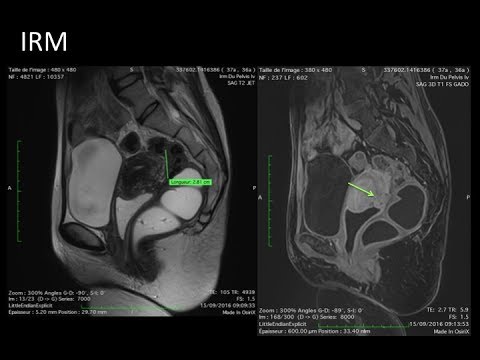

Hellow guys, Welcome to my website, and you are watching 2015-01-26- Chirurgie conservatrice avec symétrisation (6). and this vIdeo is uploaded by Mohammed Ezzet Charfi at 2015-11-23T17:55:30-08:00. We are pramote this video only for entertainment and educational perpose only. So, I hop you like our website.